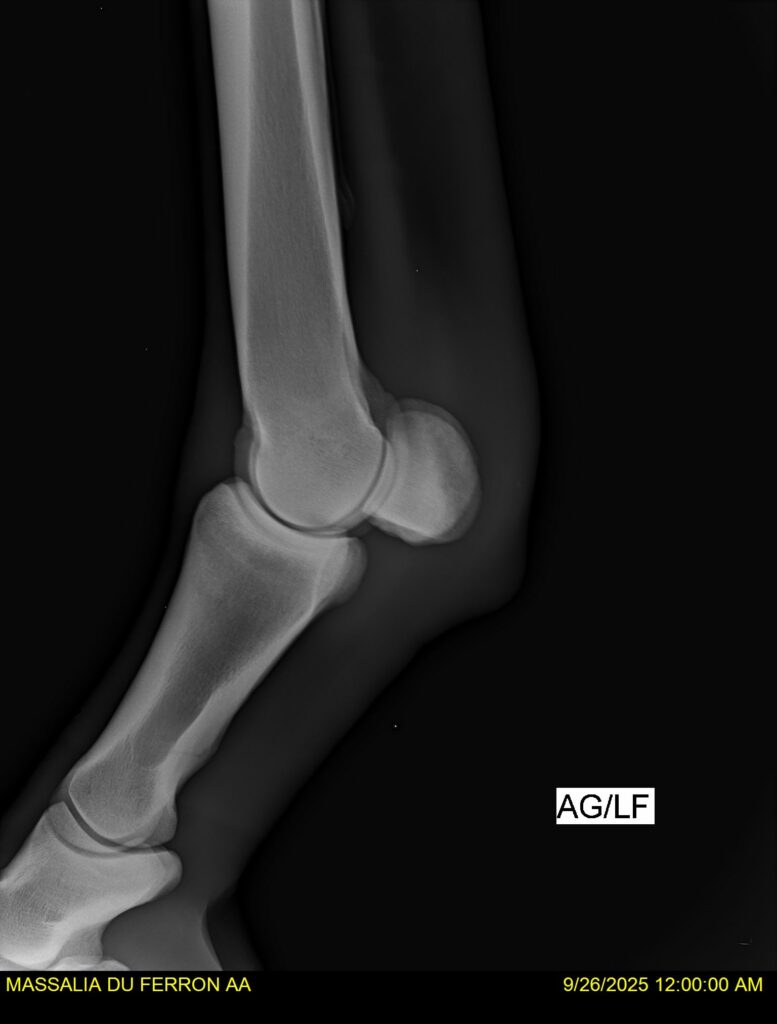

MASSALIA DU FERRON, jument qui prendra 4 ans par PRESTIGE KALONE x TRESOR DU RENOM. Un mental en or et un véritable sens de la barre ! Facile d’accès ! Bonne énergie et bons moyens. Souche moderne et très intéressante. Transport OK, maréchalerie OK, santé RAS, Bilan clichés radios OK.

RADIOS et COMPTE RENDU